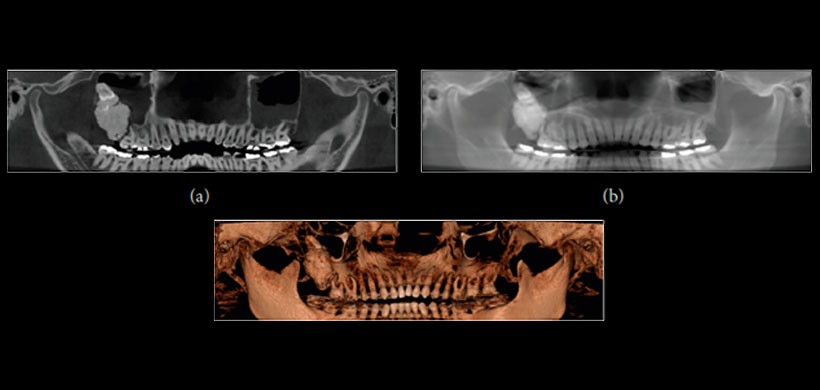

El presente reporte es un paciente de sexo masculino que  fue remitido al Departamento de Cirugía Oral y Maxilofacial, Universidad de Montes Claros, con la principal queja de dolor en la región posterior de la maxilar derecho. Las reformaciones panorámicas y los cortes obtenidos de la CBCT mostraron una masa radiopaca irregular rodeada por una distinta llanta radiolúcida asociada con el tercer molar superior derecho, en estrecha relación con el seno maxilar.  (Figura 1 y Figura 2) Posterior a la cirugía, se realizó un escaneo de micro – CT de la muestra obtenida y se obtuvo la adquisición usando una máquina SkyScan 1172 (Bruker SkyScan , Aartselaar , Bélgica ). En la cual se observó material en la periferia de la lesión ( Figuras 3 ( b) y 3 ( c) , flechas blancas ), que es compatible con esmalte de los dientes y áreas hipodensas (Figuras 3 (b) y 3 (C), flechas negras)  compatibles con el tejido de la pulpa siendo el diagnóstico definitivo  de odontoma complejo .

Figura 1: Reformaciones panorámicas de la tomografía volumétrica de haz cónico